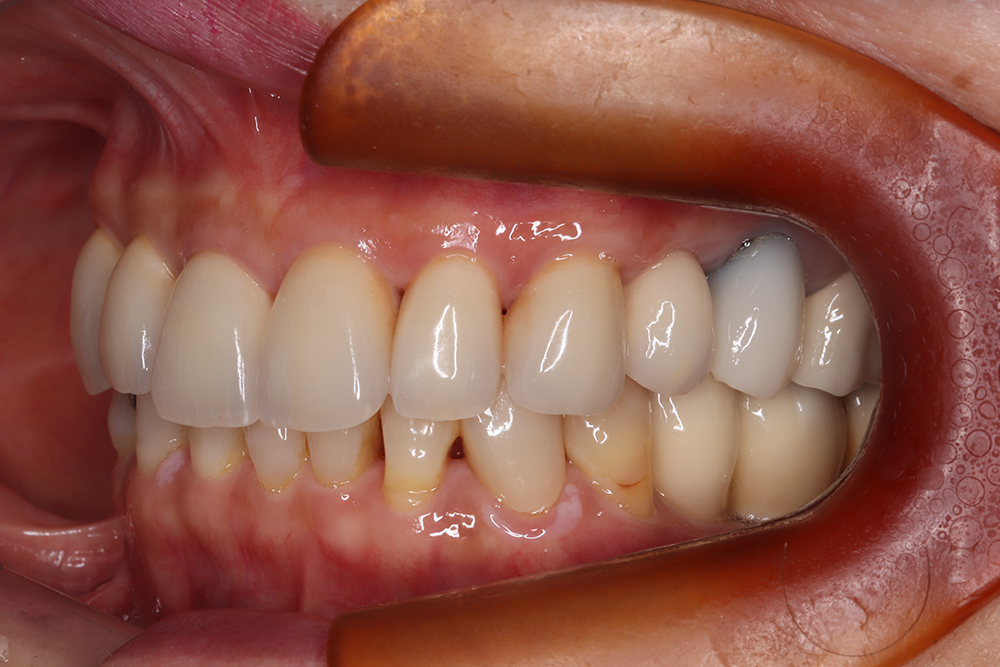

64歳 女性 紹介患者様

- 主訴

- 上下左右の歯が無くて、食べずらい、右下の歯が痛い

- 処置内容

- 右上3本、左上1本、右下3本、左下3本、鎮静麻酔

- 治療費用

- 上顎:約180万円(税込)下顎:約170万円(税込)

- 治療期間

- 上顎:約9か月、下顎:約6か月

- リスク

-

術後の腫れ、痛み(ピークは3日後、1週間で軽減)

上部構造物、仮歯の破折、人工歯根脱落リスクがあります